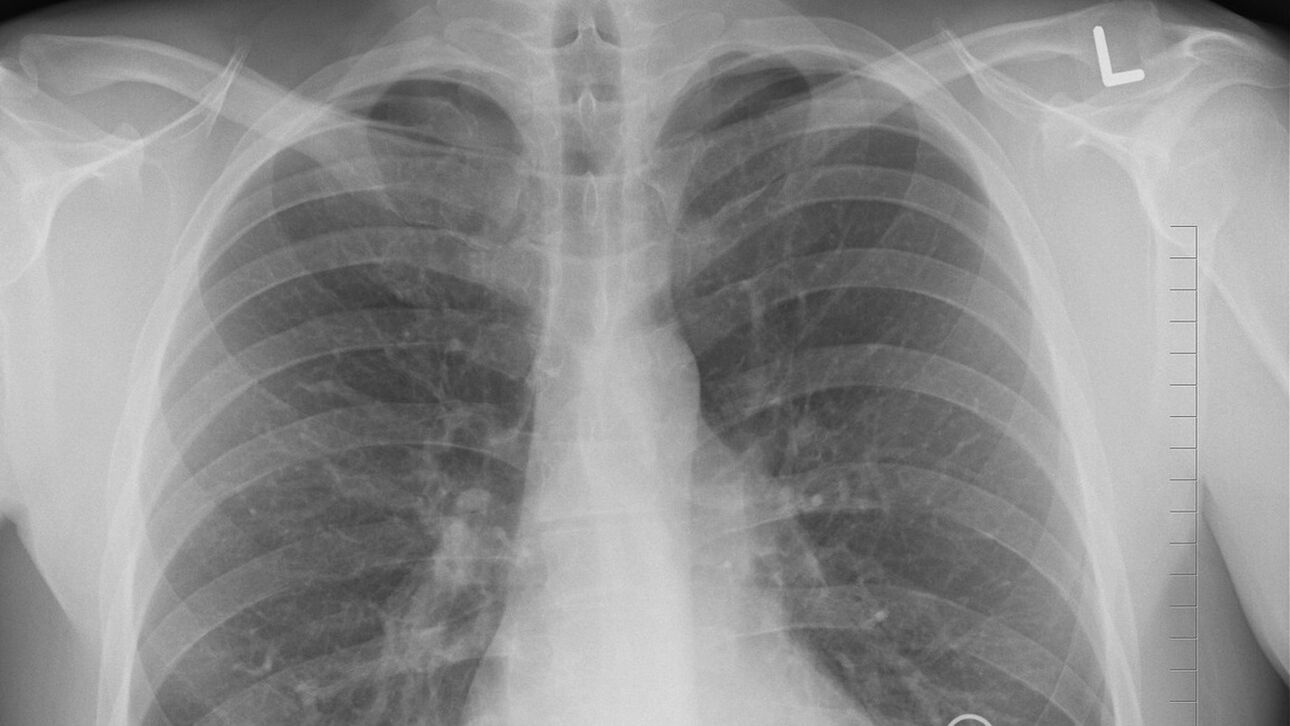

Η πνευμονία είναι μια λοίμωξη των πνευμόνων που μπορεί να προκληθεί από μια ποικιλία παθογόνων παραγόντων, συμπεριλαμβανομένων ιών, βακτηρίων και μυκήτων.

Όταν έχετε πνευμονία, στους μικροσκοπικούς σάκους αέρα στα πνευμόνια σας δημιουργούνται φλεγμονές, που μπορεί να γεμίσουν με υγρό ή ακόμα και πύο.